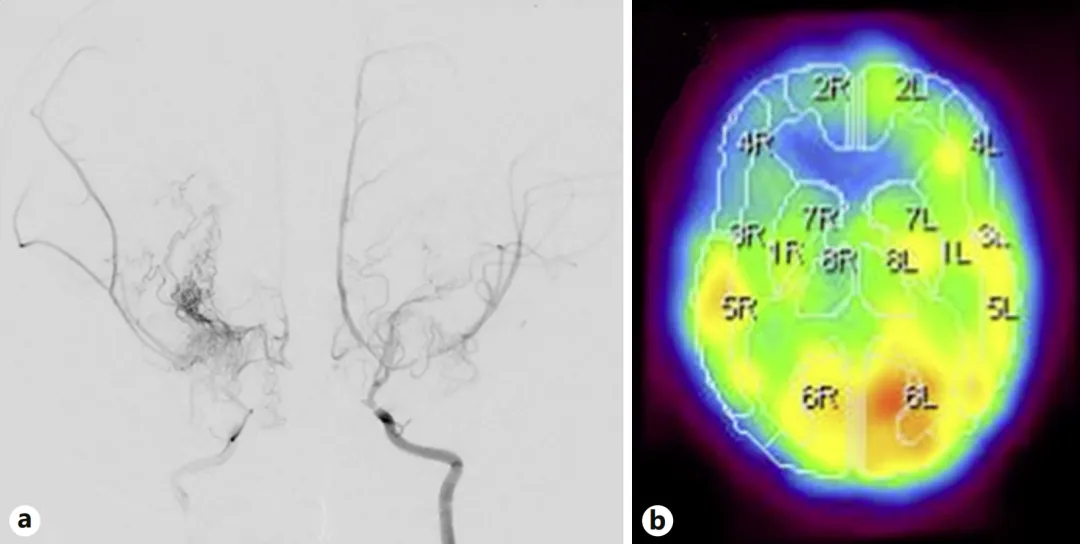

患儿桃子2岁时突发惊厥就诊,此前已有多次不明原因猝倒发作。头部磁共振成像(MRI)检查显示脑梗死存在,进一步经磁共振血管造影(MRA)和数字减影血管造影(DSA)确诊为烟雾病。详细检查发现:

MRI确认脑梗死病灶

DSA显示双侧颈内动脉末端、大脑前动脉近端及大脑中动脉严重狭窄

123I-IMP SPECT证实右侧额叶脑血流显著减少,与既往脑梗死区域吻合

患儿血管病变为双侧性,表明双侧大脑半球均处于缺血高危状态。由于烟雾病缺乏特效药物治疗,血管重建手术成为改善脑血流、预防缺血性脑卒中复发的唯一有效方案。